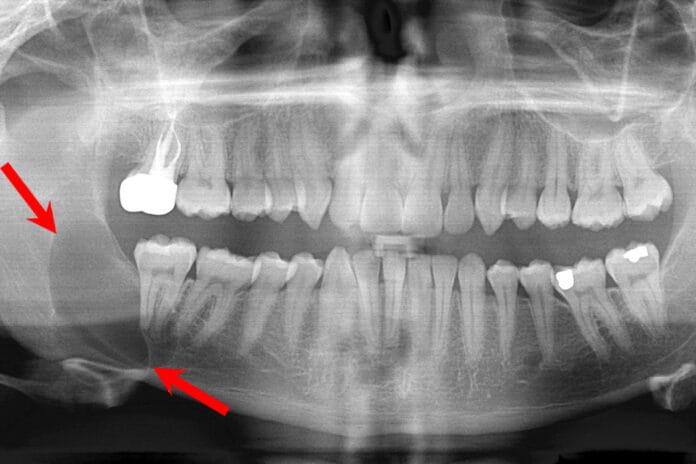

Oral Pathology: Distinguishing Cysts From Abscesses

Recently, I encountered two situations that inspired this article. I came across a periapical radiograph of a new patient with a radiolucency, presenting as...